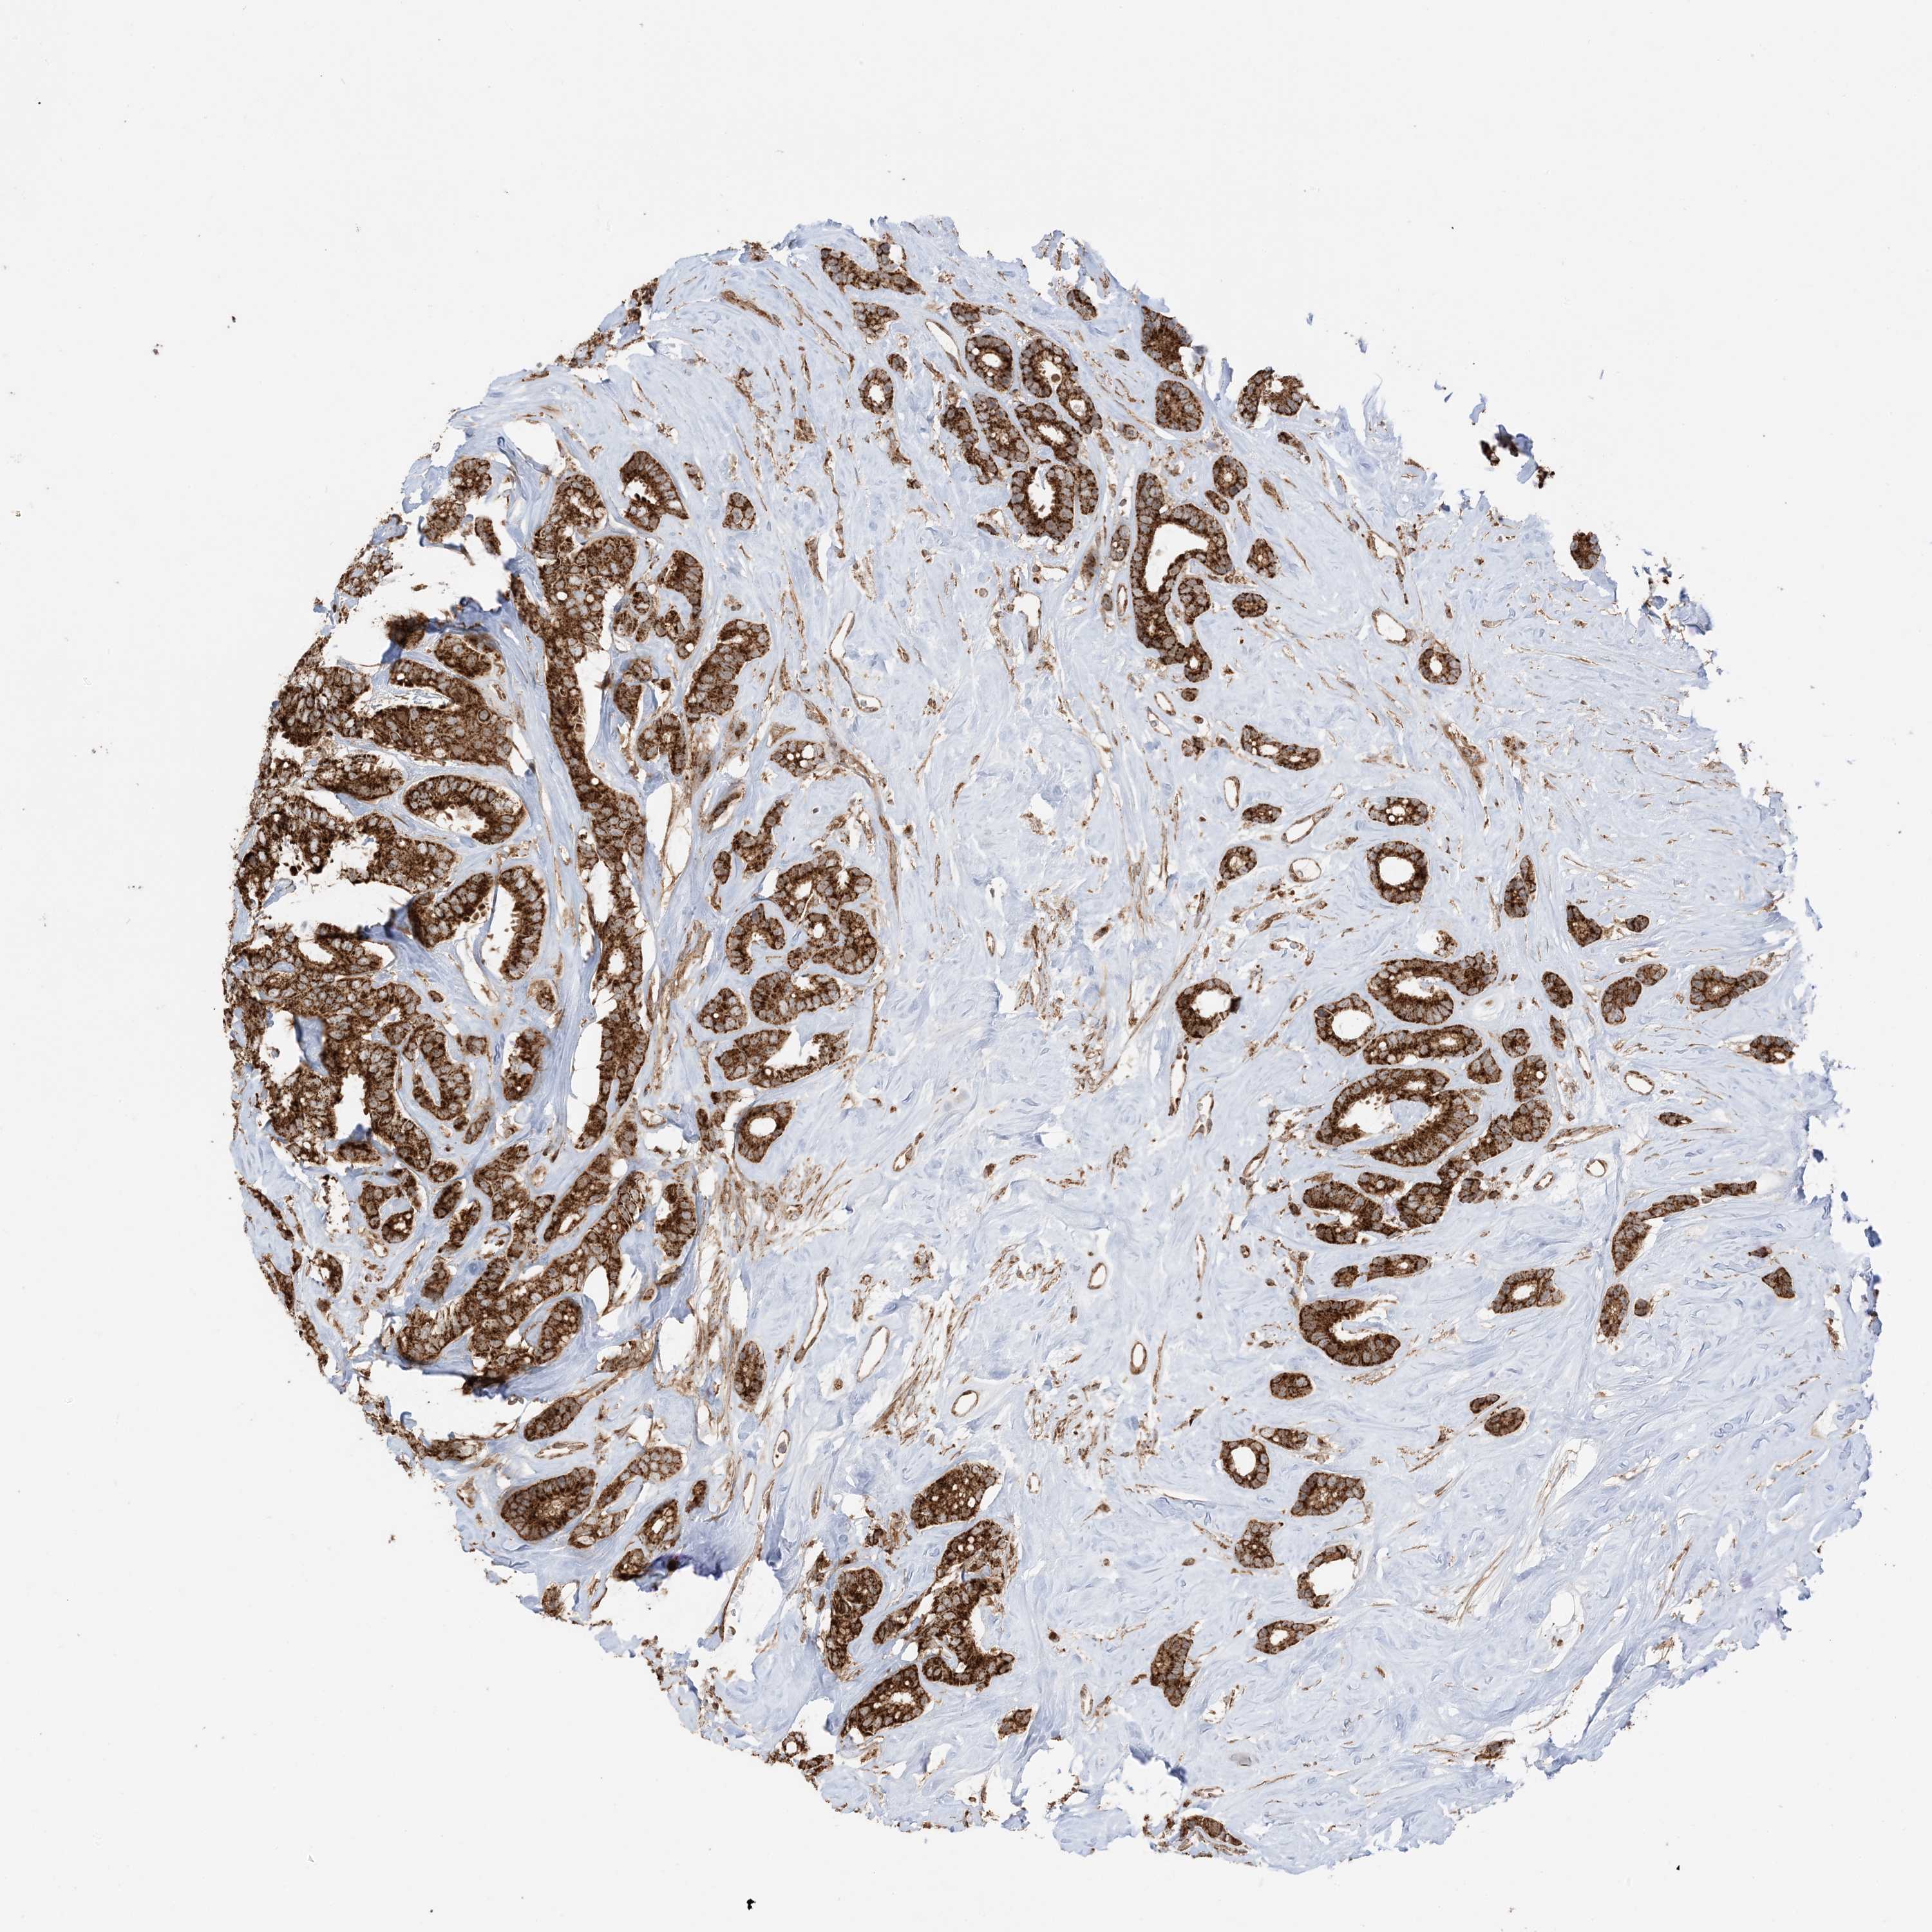

CANCER BREAST CANCER Show tissue menu

BRCA TCGA BRCA VALIDATION PROTEIN EXPRESSION